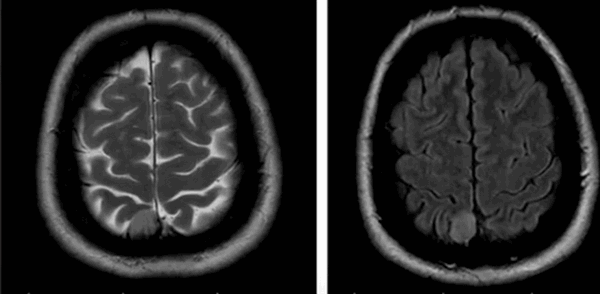

До- и постконтрастное изображение злокачественной опухоли головного мозга

С помощью МРТ при раке мозга выявляют локализацию опухоли, степень ее инвазии в соседние структуры, особенности кровоснабжения, стадию заболевания и наличие метастазов. Для получения дополнительных сведений, сканирование проводят в различных последовательностях (Т1, Т2, FLAIR, диффузно-взвешенное и пр.), в нативном режиме и после контрастирования.

В некоторых случаях МРТ диагностика опухолей головного мозга бывает затруднена. Гипоэхогенные образования без четких контуров могут быть перепутаны с признаками ишемического инсульта. Аппараты с низкой степенью напряжения магнитного поля и ограниченным пространственным разрешением могут «не увидеть» образование. Для диагностики патологий мозга применяют томографы мощностью от 1,5 Тл. Практически всегда дополнительно проводится МР-сканирование с контрастированием для улучшения визуализации новообразований.

МРТ ― безопасная и высоко информативная диагностическая процедура. Отсутствие лучевой нагрузки позволяет проводить ее столько раз, сколько нужно для контроля состояния больного. Метод актуален для предварительной оценки степени злокачественности образования, повреждения близлежащих структур, особенностей кровоснабжения опухоли. По результатам сканирования врач уточняет сохранность функций мозга, опасности заболевания и составляет план обследования или лечения. Своевременное выявление опухоли в мозге может спасти человеку жизнь. Поэтому роль МРТ в диагностике и лечении онкопатологии ЦНС чрезвычайно велика.